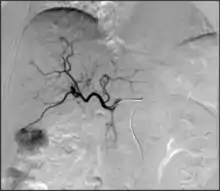

- Embolization: Placement of a metallic coil or embolic substance (gel-foam, poly-vinyl alcohol) to block blood through to a blood vessel, either to stop bleeding or decrease blood flow to a target organ or tissue.[7]

- Embolization: The goal of embolization is to decrease or stop flow only in a target vessel, while avoiding cutting off the flow to nearby non-target vessels. This can be performed to stop active bleeding (as in trauma[82]) to limit anticipated blood loss (such as in a complex surgery,) or to cut off blood supply to either an abnormal vessel (e.g., aneurysm[83]) or abnormal structure (e.g., tumor.) There are many embolic agents available, from metallic plugs and coils to various biologically compatible particles and glues.[84] Depending on the clinical situation, embolization can be temporary or permanent.